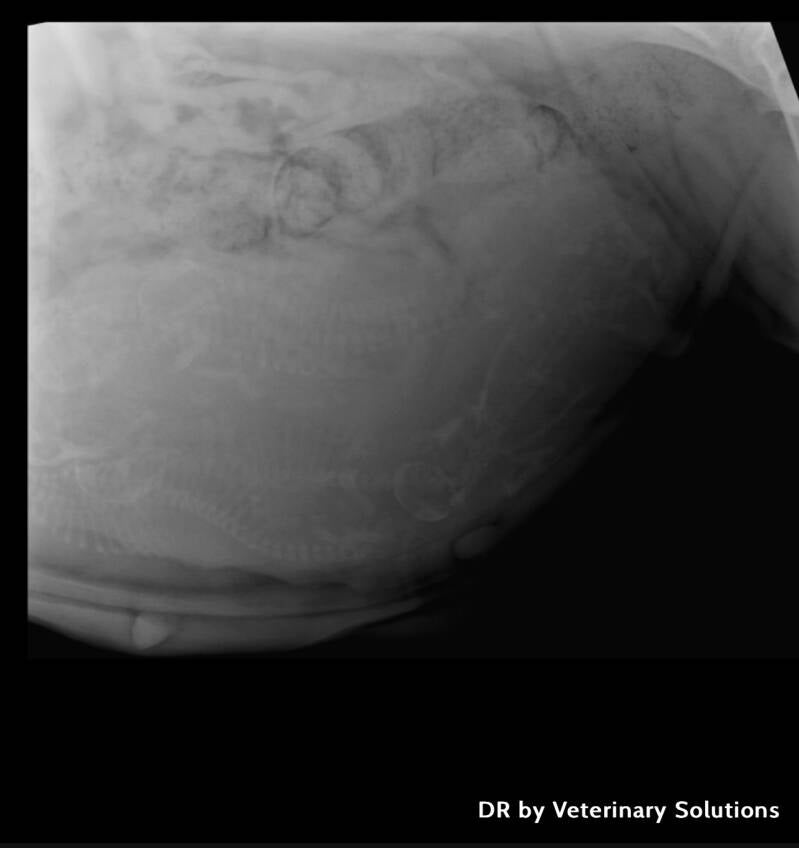

2 mei ongeveer een week voor de bevalling hebben we deze foto's laten maken, Omdat haar buik zo groot is zijn ze niet echt duidelijk maar samen met de dierenarts tellen we er nu 8.

Wat ziet ze er prachtig uit zo net voor de bevalling!